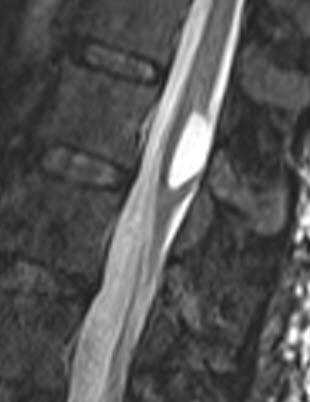

Sagittal T2 weighted MRI showing the lesion.

The patient was sent for MRI of the dorsal and lumbar spine with contrast and single voxel spectroscopy. There is a cystic intramedullary lesion inside the conus medullaris and it is stuck to the posterior wall of the dura. The content of the cyst is CSF like consistency and spectroscopy ruled out malignant changes of the lesion.

It is rare to see syringomeyletic cavity at the conus medullaris level. This was mostly triggered by the presenting arachnoidal adhesions of this area to the dural wall.